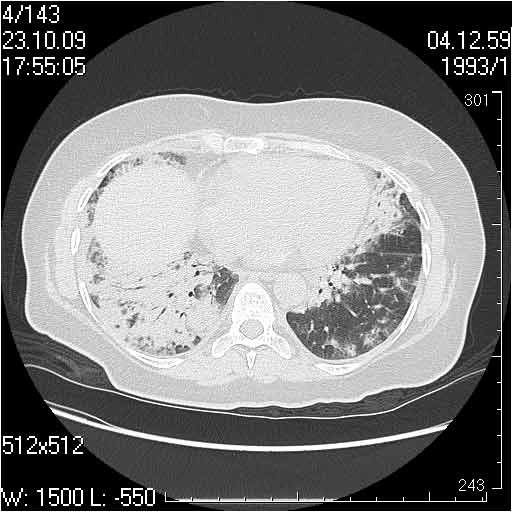

Случай №1

Женщина 50 лет.

Случай 1: изменения характерны для интерстициальной пневмонии (IIP/UIP idiopathic interstitial pneumonia/usual interstitial pneumonia); говорить о конкретной форме без открытой биопсии затруднительно.